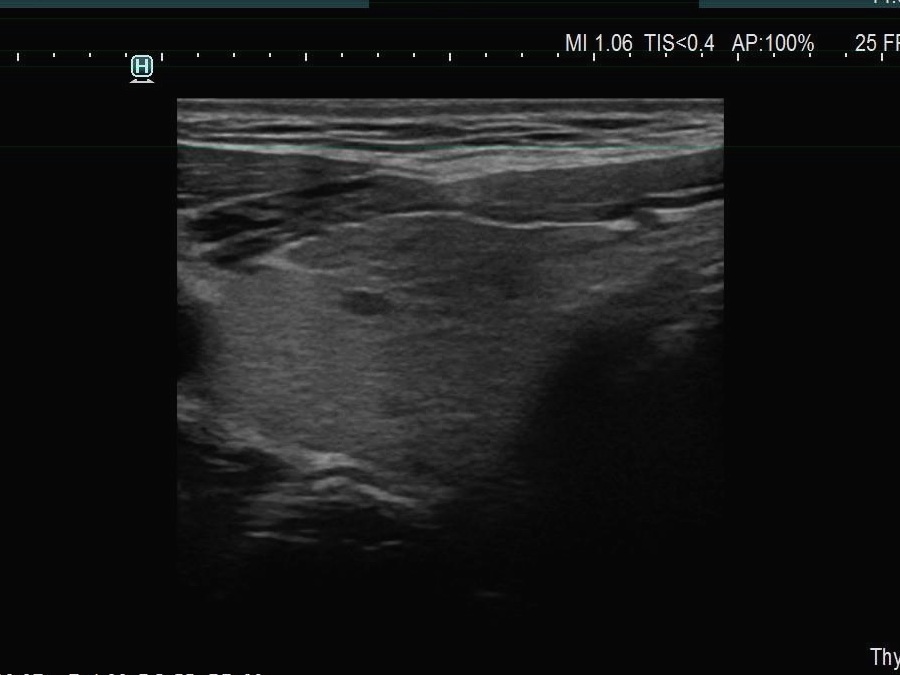

Ultrasonography. The thyroid was echonormal. There were multiple smaller lesions in the right lobe. The largest one was minimally hypoechoic and presented with halo and perinodular vascularity. A large, hypoechoic nodule occupied almost the entire left lobe. The nodule had lobulated and spiculated margins and bulged into the sternocleidomastoid muscle. The vascularity was not specific.